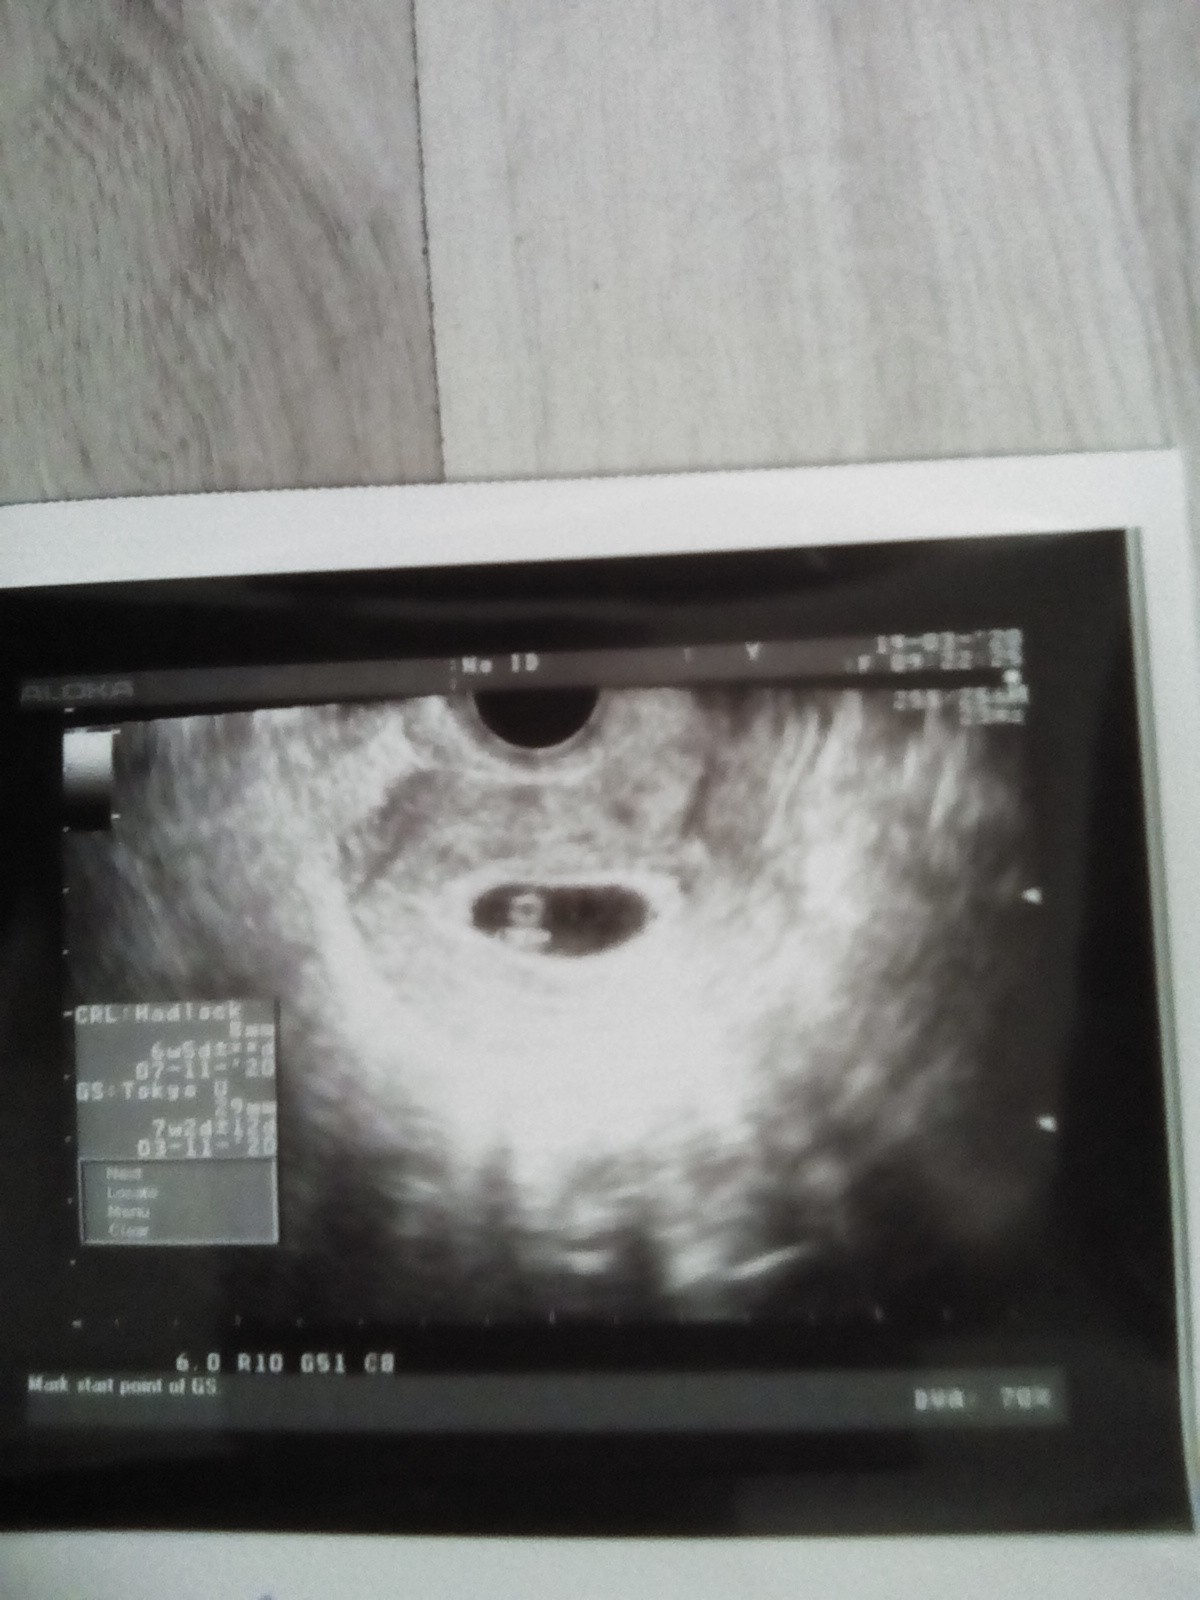

Listopadowe mamy 2020

Byłam u lekarza na NFZ ciąża jest prawidłowo umiejscowiona wg OM dziś 6t6d wg USG zarodek 8 mm z bijącym serduszkiem wskazuje na 6t5d w pęcherzyku 29mm termin wg USG 7.11 lekarz trochę z łaski przedłużył mi L4 dał skierowanie tylko na morfologię mocz i glukozę mam nadzieję że gdziekolwiek uda się zrobić miałam nadzieję że wyda skierowanie na te wszystkie potrzebne badania ale stwierdził że na kolejnej wizycie reszta litanii. Następna wizyta 2.04 a prywatną mam wcześniej 27.03 mam nadzieję że się odbędzie bo nie ukrywam ten lekarz nie był zbyt miły i miałam wrażenie ze szybko szybko i wyłaz do domu. Najważniejsze że mam już zdjęcie mojej małej istotki i wszystko jest w porządku [emoji7]